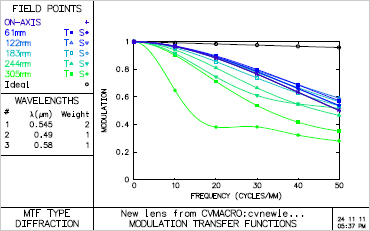

- MTF(Field)

- MTF(Frequency)